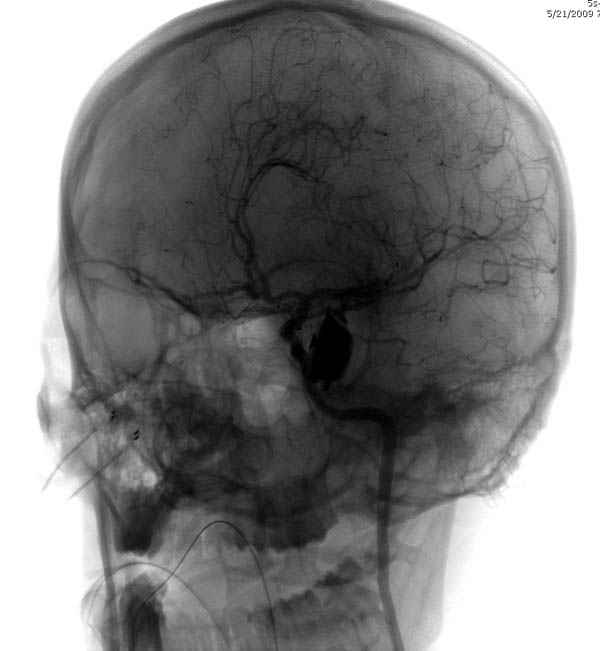

По протоколу сделаны все необходимые исследования: рентген, ангиограмма с 3Д реконструкцией, где обнаружили что все жизненно важные сосуды не задеты, даже некоторые "сидят" изгибаясь на ноже.